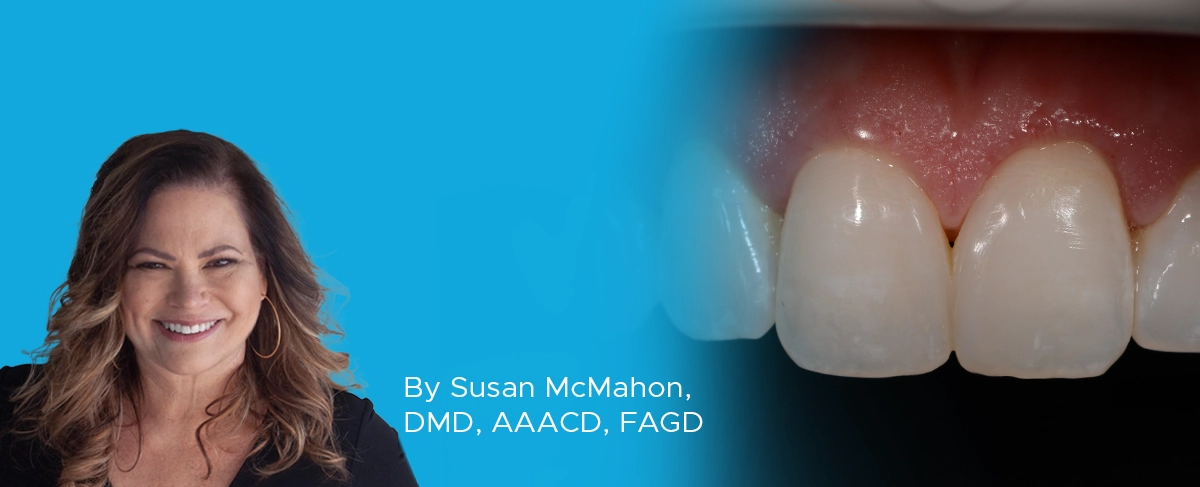

This case illustrates a common cosmetic concern I see in my practice. “I want my smile to look better. I’ve whitened my teeth and I still don’t love the way my teeth look.” This patient has very healthy and nicely shaped teeth but is dissatisfied with their appearance. Smile evaluation showed she had a black triangle between her central incisors. She also asymmetry of her gingival with her left central and lateral incisors having lower gingival margins and zeniths than her right central and laterals. (FIG. 1)

Pre-op. Note black triangle between the central incisors and the asymmetry of the gingiva with lower gingival margins on the left central and lateral incisor.